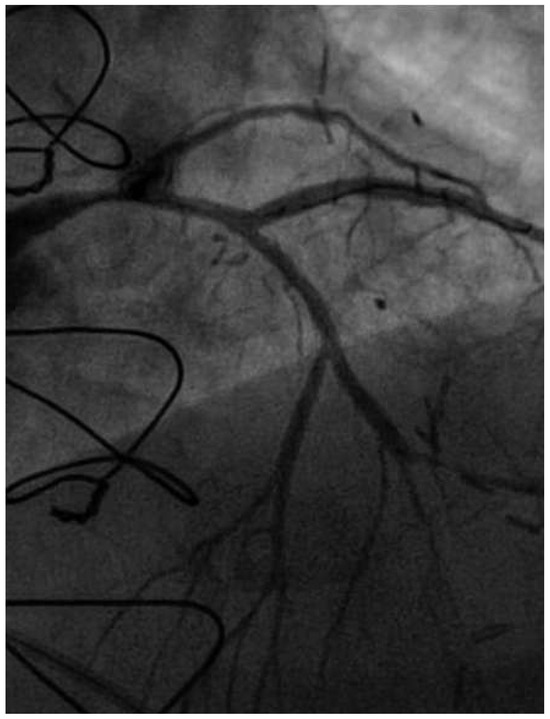

Coronary angiography of the left coronary system demonstrated severe left main stem (LMS) disease (Figure 1). The severe LAD in-stent restenosis was very eccentric and appeared to be restricting the origin of a sizeable diagonal branch, which also had severe disease. Distally, the LAD was occluded at the point where another stent had been inserted previously and just beyond a large septal perforator. The Cx had severe ostial disease and gave rise to a heavily diseased first obtuse marginal branch. The remainder of Cx and right coronary artery (RCA) systems were occluded proximally, with absent collaterals. The only patent graft was the LIMA, anastomosed very distally to the LAD (Figure 2). Following discussion, it was felt that neither Cx nor RCA were suitable targets for surgery and we therefore undertook intervention to the LMS and LAD / first diagonal bifurcation.

Figure 2. Straight PA view of the LIMA anastomosis to distal LAD.